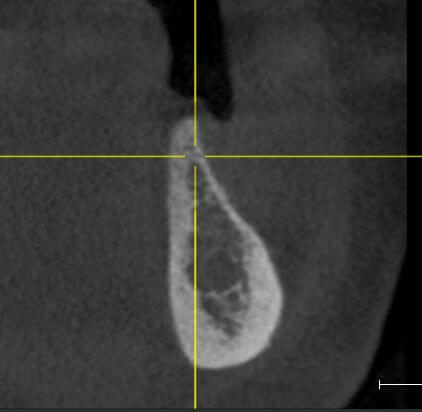

Пациент обратился с целью протезирования. На компьютерной томографии выявлен недостаток костной ткани по высоте (3−5 мм) за счет углубления гайморовой пазухи. Следующим этапом в области отсутствующих зубов 1.5, 1.6 и 1.7 планируется дентальная имплантация.

Врачом А.Г. Геворкяном выполнена операция по наращиванию костной ткани (открытый синуслифтинг). На контрольном снимке определяется увеличение объема костной ткани по высоте.